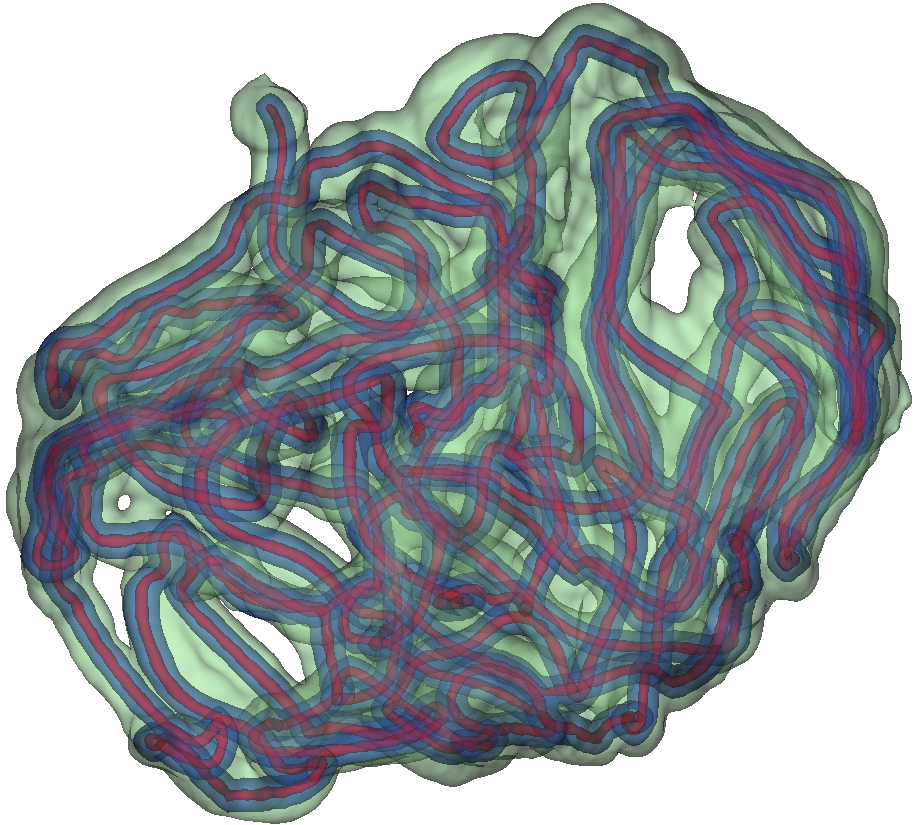

Fig. 3 shows example segmentation results. The proposed method eliminates false positives on the large bowel by the help of the applied topological constraint. Fig. 4 further clarifies the effectiveness of the proposed method by presenting 3D rendered segmentations. The proposed method produces a more topologically correct segmentation of the small bowel with fewer false positives. Fig. 5 presents example barcode diagrams, which again show the reduced numbers of connected components and holes within the segmentation result of the proposed method.

A

B

C

D